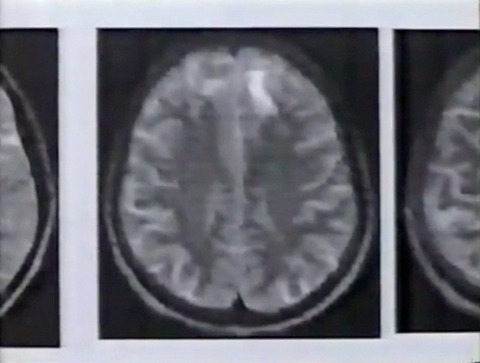

脳の状態に問題はないのか。MRIという画像診断装置を使って、詳しい検査を受けます。

その結果、脳に異常が発見されました。

前頭葉と呼ばれる、脳の前の部分に白い塊があります。神経細胞が死滅したあとです。前頭葉は、計算や思考など、創造的な働きを担う中枢です。ウラジミルさんの知的障害の原因は、ここにあるのではないかと医師たちは考えています。

脳の更に深い部分にも、神経細胞が死滅したあとがありました。ウラジミルさんの疲労感や脱力感の原因は、これではないかと診断されました。